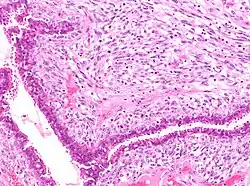

Squamous cell carcinoma of cervix | Invasive Squamous Carcinoma of the Cervix. Cold Knife Cone. | Category: Histopathology of squamous cell carcinoma of the cervix | Invasive squamous carcinoma of cervix |

![]() |